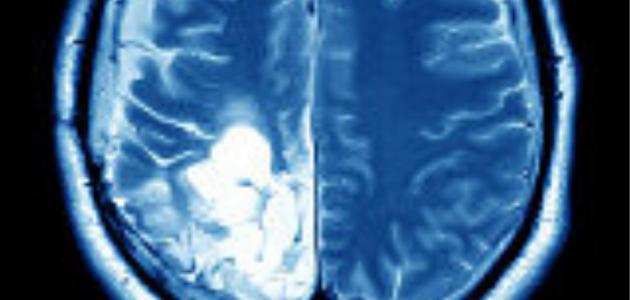

آثار ورم الدماغ

آثار ورم الدماغ ‘); } ورم الدماغ ورم الدماغ هو تشكّل كتلة أو نمو للخلايا غير الطّبيعية في الدّماغ،[١] والدّماغ هو أحد أعضاء الجسم التي تتكوّن من خلايا عصبيّة وأنسجة داعمة، مثل: الخلايا الدّبقية، والسّحايا، ويتكوّن الدّماغ من ثلاثة أجزاء…